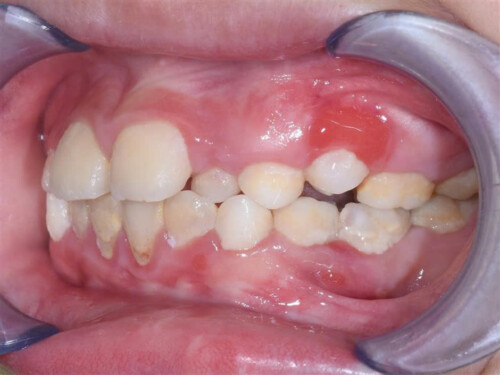

II.TRIỆU CHỨNG BỆNH VIÊM LỢI

Bệnh viêm lợi thường ít khi đau vì vậy người bệnh có thể bị viêm mà không biết. Các dấu hiệu và triệu chứng viêm lợi có thể có là:

- Lợi sưng nề

- Lợi teo rút

- Lợi chảy máu một cách dễ dàng khi dùng bàn chải đánh răng hoặc chỉ nha khoa, có thể nhận biết qua màu đỏ hoặc hồng trên bàn chải hay chỉ nha khoa

- Sự thay đổi màu sắc lợi răng từ một màu hồng khỏe mạnh đến nâu sẫm đỏ

Chẩn đoán viêm lợi cần dựa vào triệu chứng viêm lợi như: lợi sưng đỏ, có mảng bám và dễ chảy máu. Bên cạnh đó cần kiểm tra cả răng, lợi răng và lưỡi một cách tổng quát, tìm các mảng bám và cao răng tích tụ để chẩn đoán nguyên nhân